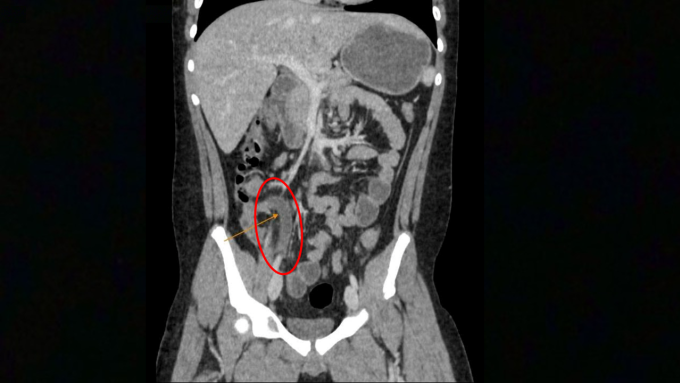

Tại Phòng khám Đa khoa Tâm Anh Quận 7 (TP HCM), kết quả xét nghiệm máu cho thấy các chỉ số viêm nhiễm của Hưng tăng vọt một cách đáng báo động: bạch cầu lên tới 22.74 K/ul (cao hơn gấp đôi mức bình thường dưới 10 K/ul) và chỉ số CRP tăng gấp 4 lần, cho thấy tình trạng viêm nhiễm cấp tính nghiêm trọng. Hình ảnh chụp CT-Scan sau đó hé lộ nguyên nhân thực sự: ruột thừa của Hưng có đường kính 12 mm (vượt xa mức 6 mm báo hiệu viêm) và bị bít tắc bởi một sỏi phân kích thước 8 mm. Chính viên sỏi này đã làm tăng áp lực bên trong ruột thừa, chèn ép mạch máu, dẫn đến tình trạng viêm hoại tử và vỡ ruột thừa chỉ trong thời gian ngắn, đòi hỏi phải phẫu thuật cấp cứu khẩn cấp.